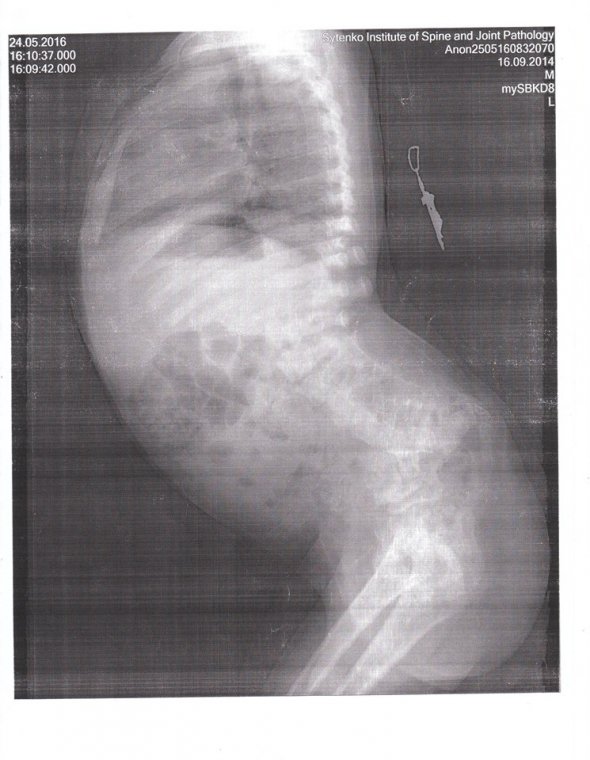

Артур Воловик, 2,8 роки, з міста Нікополь Дніпропетровської області має вади розвитку хребта. Допомогти здолати недугу обіцяють в Ізраїлі. Можуть вставити конструкцію, яка розтягуватиме хребет. На обстеження хлопчика потрібні $3 тис. Після випишуть рахунок на операцію і реабілітацію.

В Україні нам вже не можуть допомогти. Я недавно зв'язалася з клінікою в Тель-Авіві. Вони сказали, що в хребет вставлять конструкцію, яка буде його витягувати. І він буде рости разом з дитиною до закінчення зони його росту. Приблизно до 16 років. Для початку вони хочуть провести додаткове обстеження. Тому звертаюся до небайдужих людей допомогти мені зібрати цю суму", - розповіла Gazeta.ua мати Людмила Воловик.